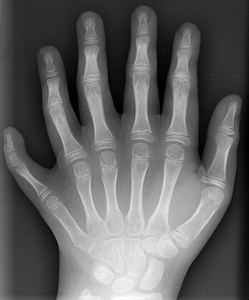

Brazilian family with six fingers and toes on hands and feet.

Subject to this 835th contact report, also with real photos attached below:

關於第835次接觸報告的主題,附有真實照片如下:

14 Members of a Family From Brazil Have Six Limbs

on Each Hand and Foot.

巴西的一個家庭有14個成員,每隻手和每隻腳都有六個指頭。

They Make the Best of It – as Piano Players or Goalkeepers.

A family with a special genetic mutation lives near the Brazilian capital Brasilia: 14 of the 23 family members have six fingers on each hand and six toes on each foot. The reason for the anatomical peculiarity in the Da Silvas is polydactyly, a rare genetic disorder. (… when earthly scientists are so stupid that they claim things from which even a complete idiot must recognise the imbecility of the whole thing …)

在巴西首都巴西利亞(Brasilia)附近,有一個家庭擁有特殊的基因突變:23個家庭成員中的14個人每隻手都有六個手指,每隻腳都有六個腳趾。這種解結構特異性是由「多指症」(polydactyly;或稱多指畸形)引起的,這是一種罕見的基因疾病。(… 如果地球科學家如此愚蠢,竟然宣稱一些連一個白癡都能辨識出其荒謬的事情 …)

This is very interesting, although it is not an anomaly, as is probably assumed by earthly scientists and called polydactyly by them. What I see here pictorially points to very distant descendants of foreigners who came to the Earth from a distant galaxy many millennia ago and mated with Earth-humans, whose descendants and again their descendants, etc., passed on physical peculiarities down to the present time, thus testifying to the immigration of foreigners to the Earth at very early times.

這非常有趣,但這不是地球科學家所認為的異常情況,也不是他們所稱之為「多指症」的異常情況。我在這裡看到的東西表明了來自遙遠外星系的後代,他們在數千年前來到地球並與地球人交配,其後代又傳承下去,一直到現代繼續傳承身體特徵,這證明了遙遠時期外星人在地球上的移民。